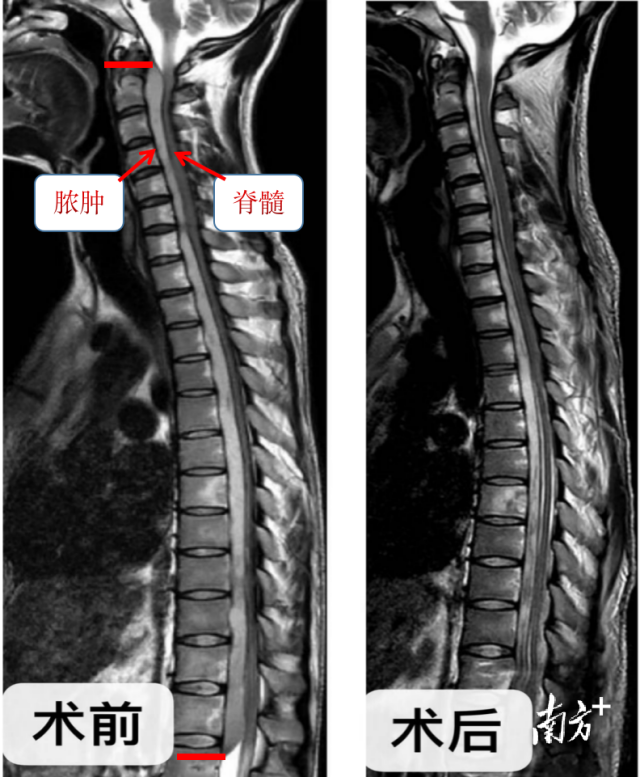

入院检查MRI显示,小陈的病变范围从颈1一直延伸至胸12节段,在长达19节椎管内的脊髓腹侧可见梭形占位。王亮判断考虑患者为椎管内结核性脓肿,脓肿长度达到了40公分!脊髓严重受压,小陈感觉颈项部疼痛强直无力、双下肢乏力的病因找到了。

南医三院是广东省骨科医院,收治过大量脊柱结核患者,然而,小陈这样的病例实属罕见。王亮介绍:“在狭长的椎管内,脊柱结核产生的脓液将颈段和胸段脊柱都泡在脓液里,而且还大量存在于脊髓的腹侧面,几乎填满了所有空隙。脓肿侵占了椎管80%以上的范围,将脊髓挤压成细条状,要彻底清除脊髓前方的脓肿,对于医生来说,是一个巨大的挑战!”若不积极处理,患者随时都有全身瘫痪的风险,医生必须在控制感染的同时,准备为患者进行手术排脓减压,将里面的脓引出来,防止脊髓出现不可逆的损伤。

术后一周经过严格的抗结核、营养支持治疗,复查MRI和感染指标,患者椎管内脓肿明显缩小,脊髓周围可见通畅的脑脊液流通,脊髓受压的问题也及时得到了解决,抽血检查感染指标得到有效控制。